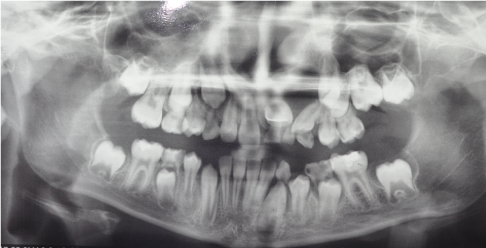

In the first year after the surgery it has been checked the progress of the healing every three months with a Ortopantomography (Figures 2-4). It has seen a reduction in cystic volume and a spontaneous eruption process. One year and half after the surgery a ortopantomography was performed and no cystic lesion was observed. 4.3, 4.4, 4.5 was completely erupted (Figure 5).

Figure 2 Case 1. Three months after the marsupialization

Figure 3 Case 1. Six months after marsupialization

Figure 4 Case 1. Nine months after marsupialization

Figure 5 Case 1. After one year and a half there is no cystic lesion and the element displaced are erupted